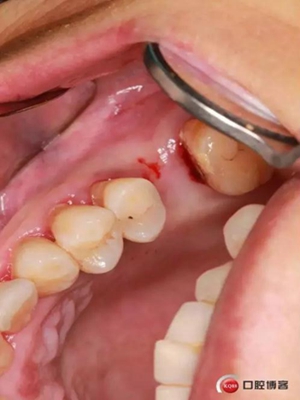

改良式外提升工具盒-外提 科貿(mào)嘉友收錄

大家好,我是梁老師的助理小依。由于梁老師每天手術(shù)檔期安排較滿,加上經(jīng)常出差講課,沒有時(shí)間整理病例 。為了方便大家更及時(shí)的了解梁老師最新手術(shù)動(dòng)態(tài),以后將由我為大家整理并推送梁老師最新經(jīng)典案例。案例文字旁白少,但圖片會(huì)盡量完整展示手術(shù)全過程,供大家學(xué)習(xí)參考。有任何問題,可以留言,梁老師會(huì)親自為大家解答。感謝大家對梁老師的支持和關(guān)注!